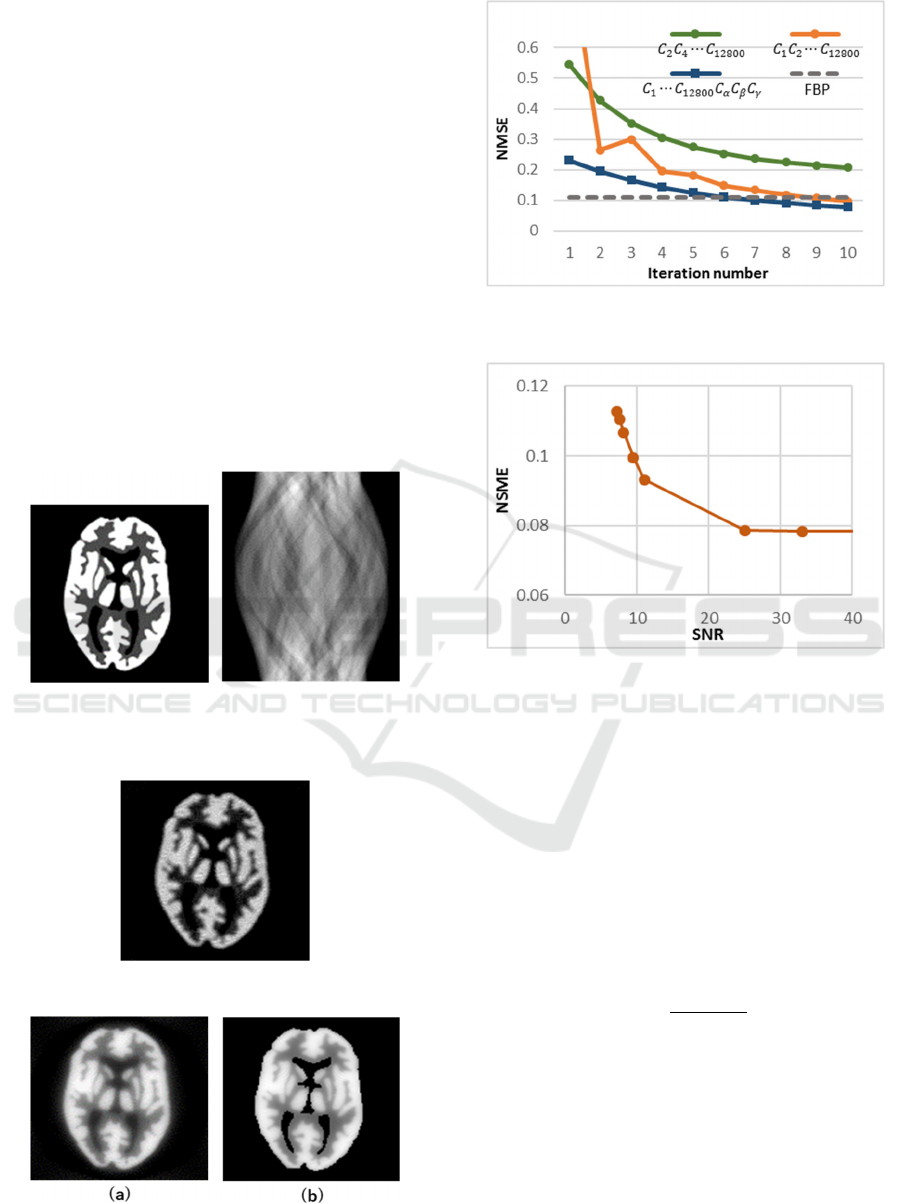

Figure 5: The reconstructed image using (a) ART (10

(10 iterations).

iteration number.

SNR.

Our first image is a text based phantom. Figure 3

Figure 8: The original test image 2 (128×128pixel, 8bpp)

Figure 10: The reconstructed image using (a) ART (10

Figure 6 illustrates the plots of the normalized mean

the original image. In Fig. 6 the green line shows the

NMSE by FBP for reference. From Fig. 6 we can see

Figure 7 illustrates the plots of the normalized

Our second image is 2-demensional numerical

Figure 9 shows the reconstructed image with FBP for

with three prior constraints. Figure 11 illustrates the

projections and the number of iterations. Figure 12